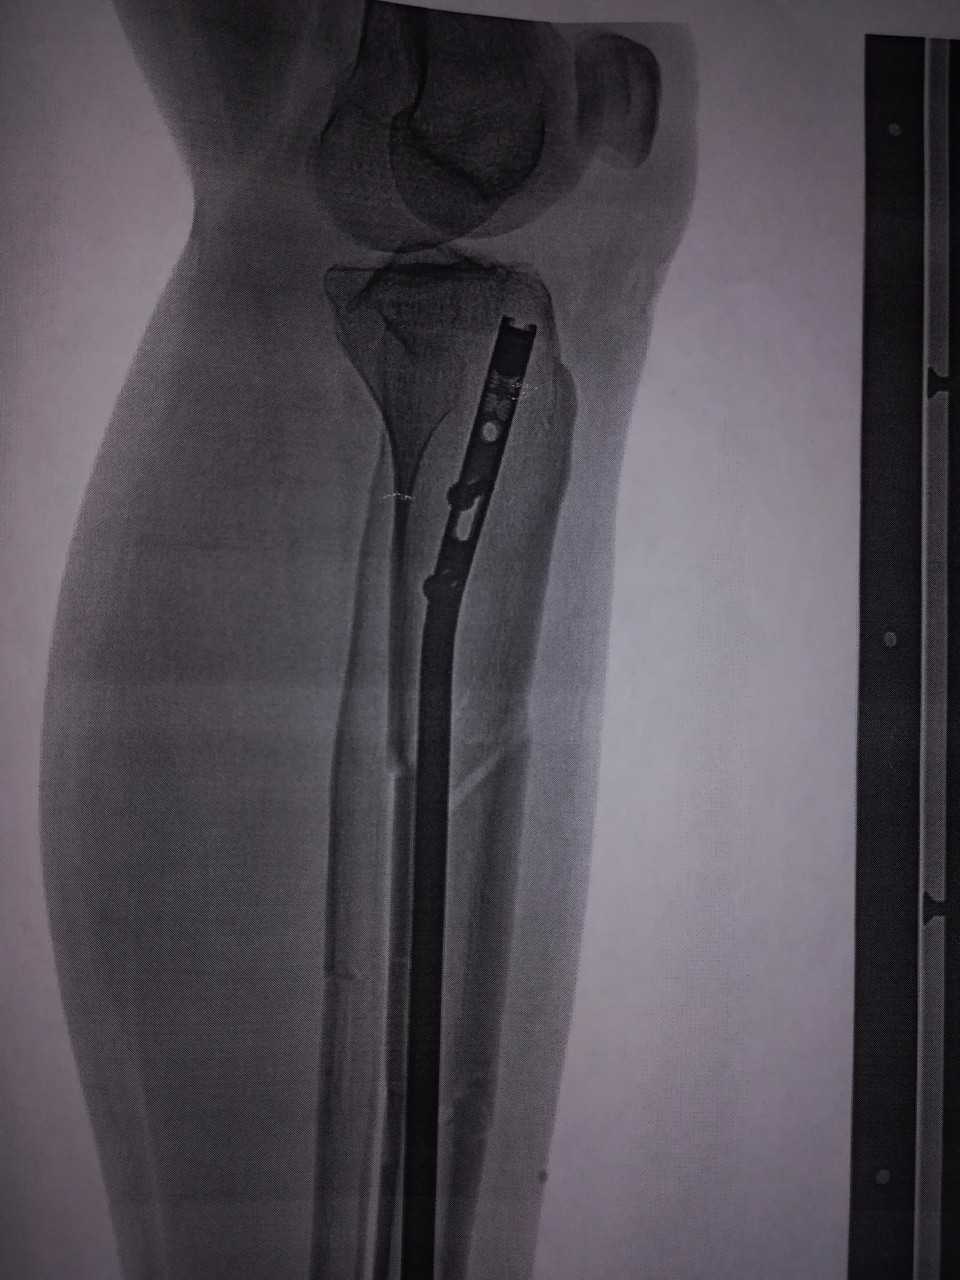

Перелом большой берцовой кости - серьезное повреждение, сопровождающееся болезненными ощущениями и нарушением функции ноги. На этой странице вы найдете много фотографий, позволяющих вам более детально изучить эту травму.

Интрамедуллярный остеосинтез

Медицинские изображения

Здесь представлены медицинские изображения переломов большой берцовой кости, сделанные врачами в процессе диагностики и лечения. Вы сможете увидеть, как выглядит этот тип травмы на рентгеновских снимках и других медицинских изображениях.